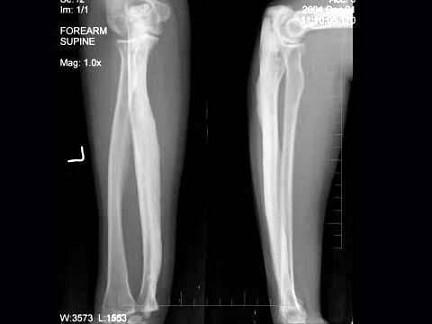

问题 30岁,女,因左前臂酸胀不适1年,活动可,左前臂正侧位片如图所示,最可能诊断是?(?)

选项 A.左尺骨蜡泪样骨病 B.石骨症 C.骨皮质增厚症 D.骨膜炎 E.慢性化脓性骨髓炎

答案 A